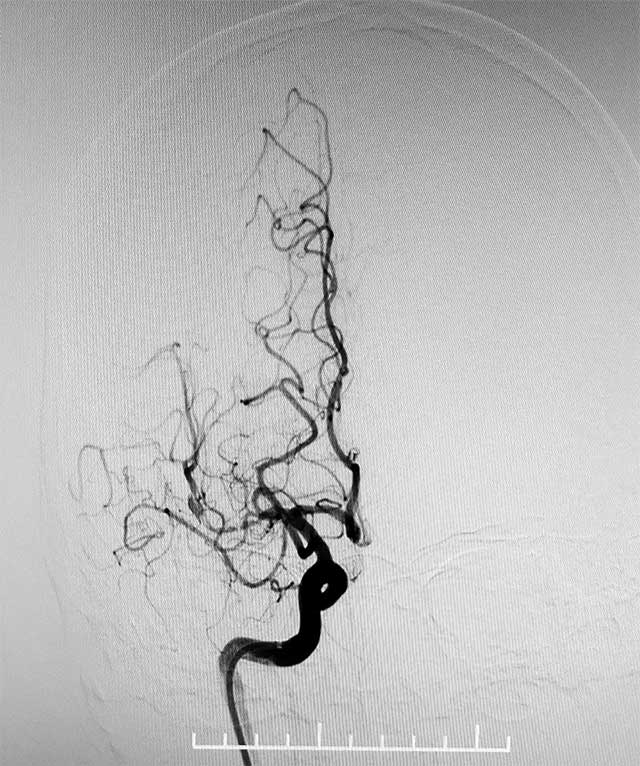

▲ 术前造影显示,右侧大脑中动脉M1段闭塞

今年4月初,转入上海蓝十字脑科医院,头颅MRA提示右侧大脑中动脉M1段闭塞,远端分支减少,右侧椎动脉V4段纤细。随后通过DSA(DSA是评价、诊断脑血管病的“金标准”,能够提供血流的动态信息,明确是否有其他血管进行代偿等)进一步评估颅内血管的情况。DSA提示:右侧大脑动脉胚胎型,右侧大脑中动脉M1段闭塞。